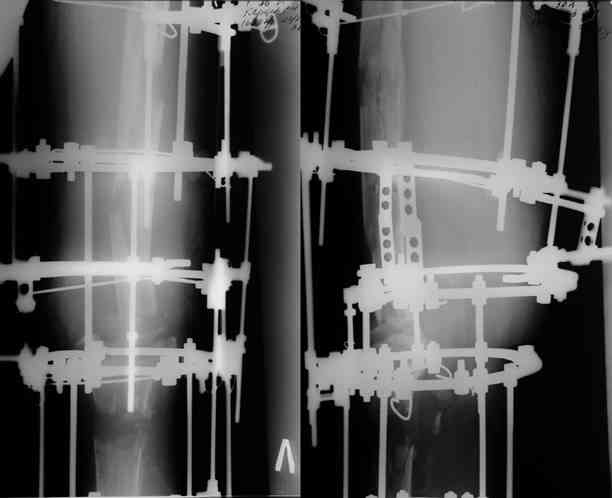

Прикрепляю пример замещения дефекта бедра 20 см, после резекции по поводу опухоли, эндопротеза Сиваша, вялотекущего остеомиелита со свищами в течении 3 лет. Получилось хорошо и всего за 6 месяцев в аппарате. Колена не было. У Вас случай сложнее. Это было в 1998г. Я работал в ЦИТО и у меня было 4 больных, я занимался им с утра до ночи. Сейчас 60 больных и операций в нашем отделении 25-30 в неделю.Если могу чем помочь - нет проблем.